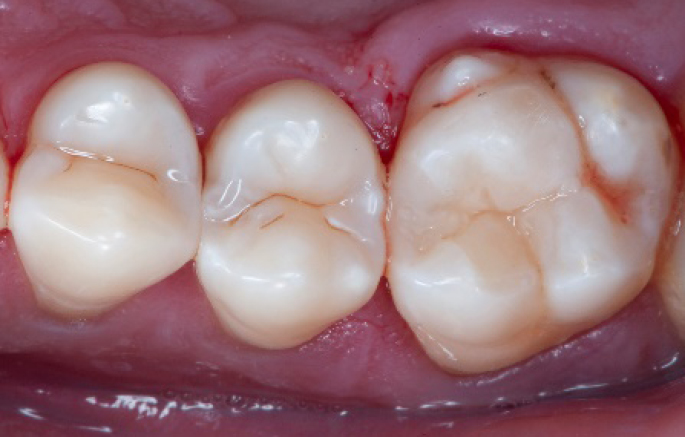

After

Final situation 2 weeks after the filling. Great comfort and no sensitivity at all were reported by the patient.

Step 14:

2 weeks control